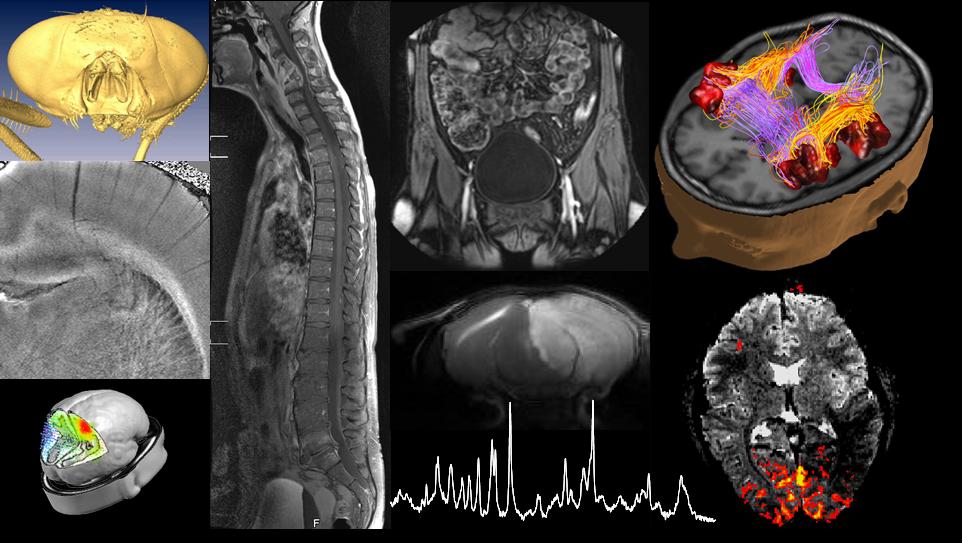

This course covers the physical principles of major in vivo bio-imaging modalities, i.e., ultrasound, computed tomography, emission computed tomography, positron emission tomography and magnetic resonance imaging. We will show how existing physical principles transcend into bio-imaging and establish an important link into life sciences, illustrating the contributions physics can make to life sciences.

In the lectures, practical examples will be shown to illustrate the respective imaging modality, its use, premise and limitations, and biological safety will be touched upon.

The student will develop a good understanding of the mechanisms leading to tissue contrast of the bio-imaging modalities covered in this course, including the inner workings of the scanner and how they define the range of possible biomedical applications.

Based on this course, the student will be able to judge which imaging modality is adequate for specific life science needs and to understand the limits and promises of each modality.